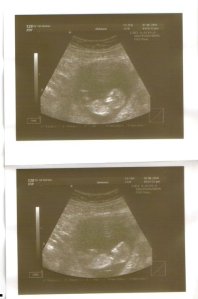

Kiama Joelle Pasley

January 4, 2011

8:32pm

3340 gms

49.5 cms

Sydney, Australia